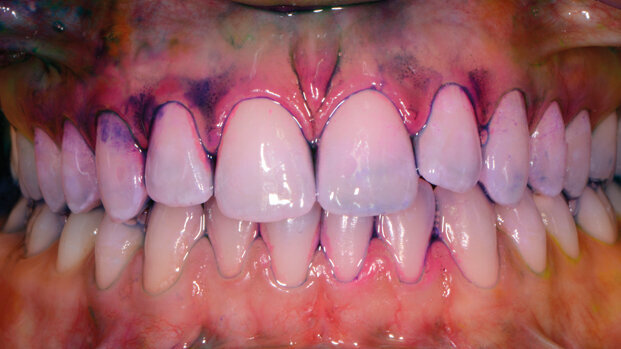

Un miglioramento rispetto alle obsolete tecniche di spazzolamento è stato rappresentato da una tecnica con ausilio colorimetrico (Checchi et al., 1998), che prevedeva l’utilizzo di un rivelatore di placca (Fig. 7) per evidenziare il biofilm e indicava al paziente di rimuoverlo con gli strumenti a sua disposizione.

Seppure questa tecnica introduca il vantaggio di rendere maggiormente visibile al paziente la placca da rimuovere, presenta il limite di non obbligarlo a scegliere lo strumento più idoneo alla sua situazione, ed è evidente che una scelta così delicata non possa essere relegata al paziente.

Da ciò nasce l’esigenza di introdurre un nuovo metodo per la gestione domiciliare del biofilm orale: il nuovo protocollo tailoring “personalizzato e condiviso”, che prevede la condivisione tra operatore e paziente della scelta delle tecnologie da utilizzare in base alla situazione clinica evidenziata e, mediante l’ausilio di rivelatore professionale bitonale, anche della selezione degli strumenti più adatti per la detersione di ogni superficie dentale; prevede, quindi, l’utilizzo dello scovolino in aggiunta allo spazzolino. Il protocollo, studiato dal gruppo di lavoro dell’Università Sapienza (prof.ssa Nardi, dott.ssa Sabatini, prof. Guerra e prof.ssa Ottolenghi), obbliga il professionista a valutare attentamente biotipo gengivale, allineamento dentale, occlusione, manualità e tipologia caratteriale, per concordare la scelta delle tecnologie, i tempi e i modi di utilizzo con il paziente.